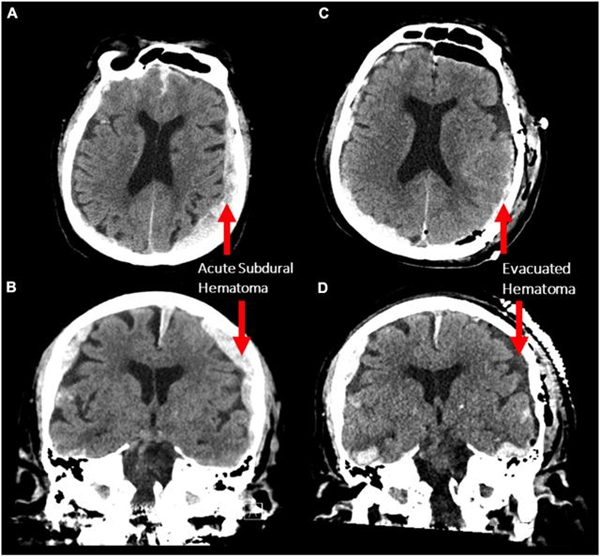

一名87岁老人跌倒后被送入爱沙尼亚(Estonia)的急诊室。患者接受了手术,但在手术后面临多达12次的癫痫发作。作为监测个体的一部分,医生使用连续脑电图(EEG)提供了一种检测癫痫发作的方法。不幸的是,患者在此期间心脏病发作去世了。而这个连续脑电图监测器首次记录了人类死亡期间的大脑活动。